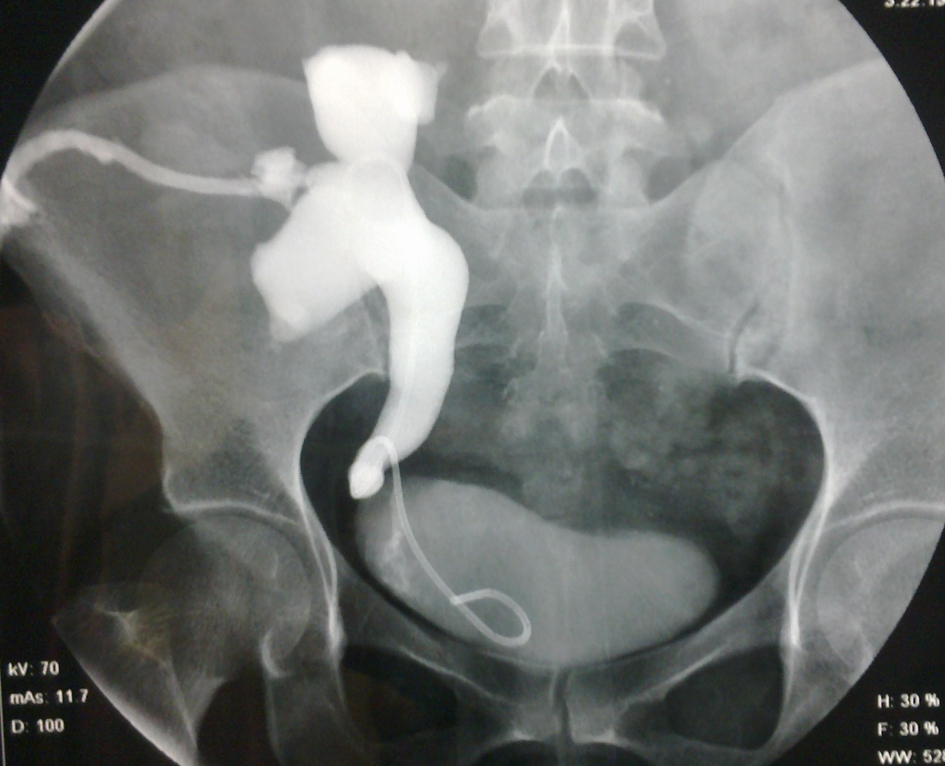

All cases of urinary leak were initially treated with prolonged catheterization. Eight out of thirteen cases responded to catheterization alone. In one out of five cases PCN (percutaneous nephrostomy) was placed even with stent in place. He did not respond to endourological management and required surgical revision which revealed terminal necrosis of ureter which required revision of anastomosis (Fig. 1, 2). Four out of five revealed leak after stent was removed which responded to PCN placement. Two patients had forgotten stent which was removed 36 and 11 months respectively. No events like stent migration, broken stent, stent related stone, hematuria or stent related obstruction was noted.

![]() Click for large image | Figure 2. Nephrostogram in same patient reveal obstruction at the ureteroneocystostomy level, later cause was found out to be ureteral necrosis. |